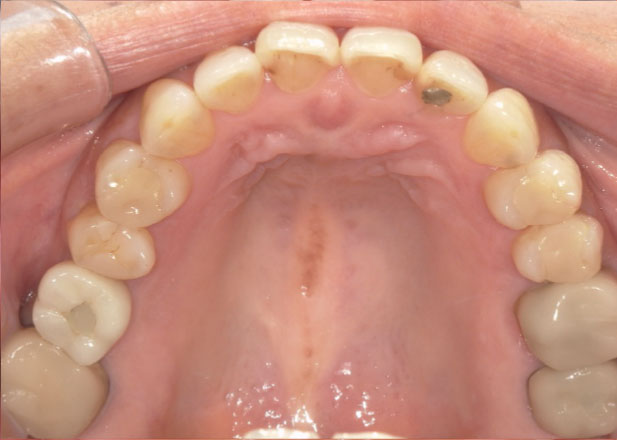

治療前

マウスピース矯正 マウスピース矯正 マウスピース矯正